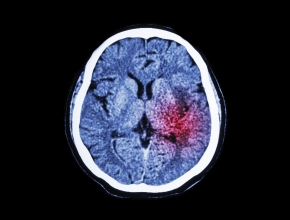

What is the “Chain of Survival” in patients with stroke in Canada?

Wieslaw Oczkowski: The “Chain of Survival” is a very interesting concept and, to be honest, when I was asked to answer some questions for this conference I had to actually look up the “Chain of Survival.” The “Chain of Survival” is a concept that I think is more common maybe in the United States and not necessarily in Canada and much more common in people with cardiological disorders.

But, in fact, we do have the “Chain of Survival” for somebody with a stroke. In somebody with a stroke it is survival and decreasing morbidity, because the difference between stroke and cardiological disease and many other disorders is that it is not just about death — it is about preventing impairment.

The “Chain of Survival” for somebody with a stroke includes education of the general public to identify the stroke warning signs. It is the chain that precedes the paramedic support services that need to identify that somebody is having a stroke and then need to triage them appropriately to the appropriate stroke services — regional or district centers, or comprehensive stroke centers versus primary stroke centers. It is the “Chain of Survival” that includes the emergency medical service that identifies the individual with stroke that then activates stroke programs within hospital services. The “Chain of Survival” proceeds to admitting people to stroke units to improve their best outcome, and a stroke unit admission requires admission to an acute stroke unit with a transfer to a rehabilitation stroke unit with a transition to the outpatient rehab services for somebody who requires rehabilitation and back to integration into the community.

I think the “Chain of Survival” for somebody with a stroke is a long chain, which starts with public awareness right to community integration.